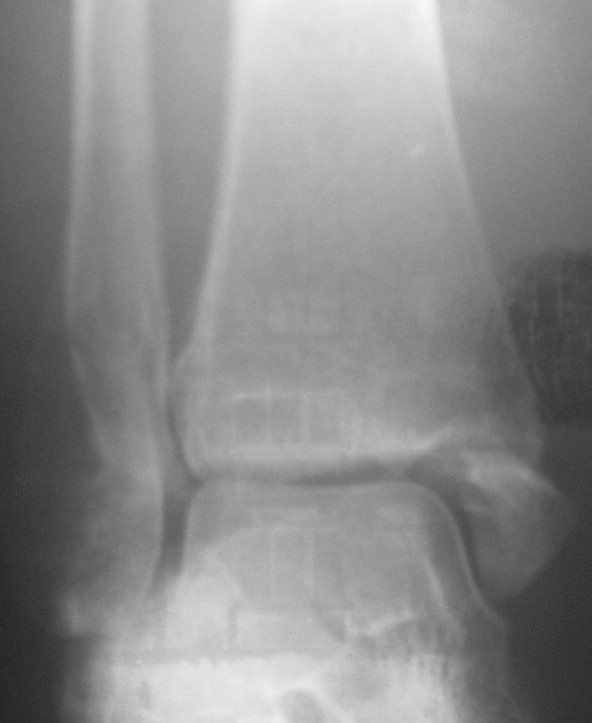

Прямой контрлатеральный сустав.JPG

Трехчетвертной контрлатеральный

На боковом довольно неплохой сустав, скудная информация о положении вилки сустава при косой рентгенограмме (Mortise view) из-за положения стопы во внутренней ротации и эквинуса во время ренгенограммы.

Рекомендуемая реконструкция: удлинение малоберцовой с исправлением ротации, исправление внутренней лодыжки с фиксацией и фиксация синдесмоза через пластины, по моему уменьшат болевой синдром у этой больной.